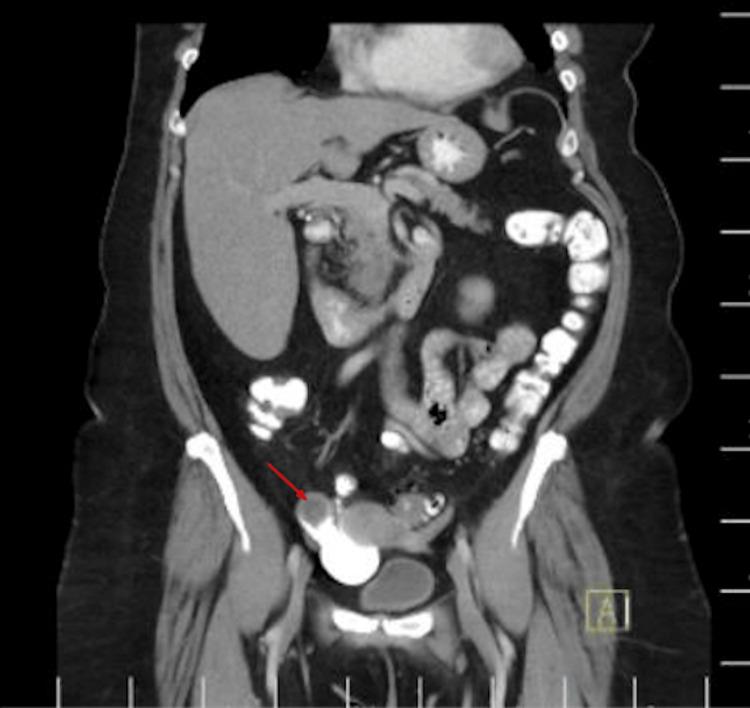

Appendiceal mucocele (AM) is characterized by the dilation of the appendix due to the accumulation of mucinous material within its lumen, often discovered incidentally on imaging. Symptoms of AM are typically nonspecific or absent, but patients may present with clinical features mimicking appendicitis or an adnexal mass. Ultrasound and CT imaging of the abdomen and pelvis are key in establishing the diagnosis. Early diagnosis is crucial, as a neoplastic mucocele can rupture, leading to pseudomyxoma peritonei (PMP), a clinical syndrome characterized by diffuse intra-abdominal gelatinous ascites with mucinous peritoneal involvement. While patients with ulcerative colitis (UC) are at increased risk for colorectal cancer, appendiceal neoplasms are rarely reported in this group. This case presentation involves a 70-year-old female patient with a history of UC who presented for a routine surveillance colonoscopy in the fall of 2024. She was diagnosed with mild UC in 2006 and had been in clinical remission since December 2018, and a colonoscopy performed in 2021 showed no mucosal inflammation. However, during the most recent surveillance colonoscopy in 2024, the appendiceal orifice was noted to be bulging, with mucus extruding, suspicious of a mucinous appendiceal neoplasm. Cold forceps biopsies were obtained, and histology showed only inflammatory changes in the appendiceal orifice. A contrast-enhanced CT of the abdomen and pelvis revealed a 3.2 x 2.0 cm tubular cystic structure originating from the base of the cecum, consistent with an AM, without signs of rupture or nodularity. The patient underwent a robotic-assisted partial cecectomy and appendectomy, and pathology confirmed a well-differentiated, low-grade appendiceal mucinous neoplasm (LAMN).

阑尾黏液囊肿(AM)的特征是由于黏液物质在阑尾腔内积聚而导致阑尾扩张,常在影像学检查时偶然发现。AM的症状通常不具特异性或无症状,但患者可能表现出类似阑尾炎或附件肿块的临床特征。腹部和盆腔的超声及CT成像对于确诊至关重要。早期诊断至关重要,因为肿瘤性黏液囊肿可能破裂,导致腹膜假黏液瘤(PMP),这是一种临床综合征,其特征为弥漫性腹腔内胶冻样腹水伴黏液性腹膜受累。虽然溃疡性结肠炎(UC)患者患结直肠癌的风险增加,但该组中阑尾肿瘤很少见。本病例报告涉及一名70岁女性患者,有UC病史,于2024年秋季接受常规结肠镜检查。她在2006年被诊断为轻度UC,自2018年12月以来一直处于临床缓解期,2021年进行的结肠镜检查未显示黏膜炎症。然而,在2024年最近一次结肠镜检查期间,发现阑尾开口膨出,有黏液挤出,怀疑为黏液性阑尾肿瘤。获取了冷活检钳活检组织,组织学检查仅显示阑尾开口有炎症改变。腹部和盆腔增强CT显示一个3.2×2.0 cm的管状囊性结构,起源于盲肠底部,符合AM,无破裂或结节迹象。患者接受了机器人辅助部分盲肠切除术和阑尾切除术,病理证实为高分化、低级别阑尾黏液性肿瘤(LAMN)。